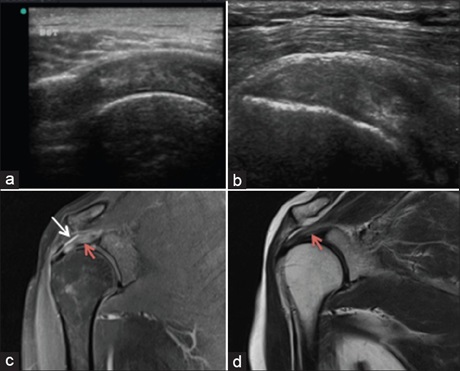

Aim: To evaluate and characterize the musculotendinous pathologies of shoulder joint using ultrasound (USG) and magnetic resonance imaging (MRI).

Background and Objectives: The glenohumeral joint, being the most mobile and unstable of all the joints, is often prone to injuries. To compensate for its unstable bony anatomy, the shoulder is protected anteriorly, posteriorly, and superiorly by a capsule and tendons that form the rotator cuff. Sonography is often considered the first-line imaging modality in the assessment of cuff as well as in nonrotator cuff disorders. MRI is of value in cases of extensive abnormality that is often incompletely characterized by the initial sonographic examination, as in case of sonographically inaccessible areas. However, musculoskeletal imaging is truly a multimodality approach and in order to identify and characterize the lesion, a combination of modalities should be used.

Results: In our study, USG showed a sensitivity of 95.2%, specificity of 88.8%, and positive predictive value of 80% for demonstrating full-thickness tears. In case of partial-thickness tears, USG showed overall sensitivity of 94.7%, specificity of 85.7%, and positive predictive value of 90%. Overall accuracy of USG in detecting full-thickness as well as partial-thickness tears was 91%.

Conclusion: In patients with shoulder complaints, USG is a reliable dynamic diagnostic tool. It reveals high diagnostic accuracy in detecting rotator cuff pathologies including cuff tears and tendinopathy. However, MRI has always been successful in overall assessment of joint structure. Its ability to evaluate labrum and various glenohumeral ligaments cannot be superseded by USG.